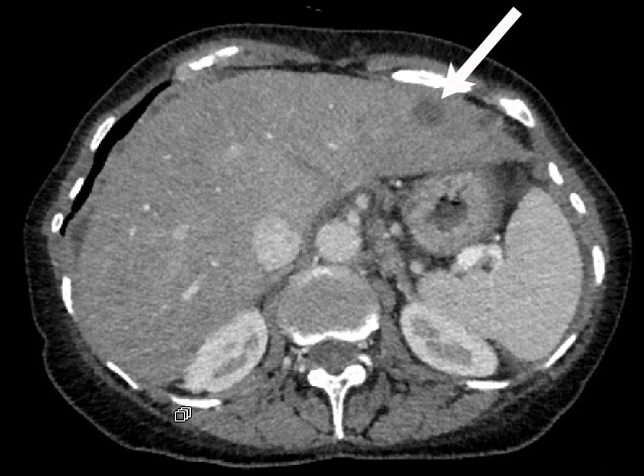

Bestätigt sich der Tumorverdacht, wird die Ausdehnung des Tumors in weiteren Untersuchungen abgeschätzt. Mittels Ultraschall und CT können Ableger (Metastasen) in der Leber ausgeschlossen werden. Weitere Untersuchungen sind: Blasenspiegelung, gynäkologische Untersuchungen sowie eine Röntgenaufnahme des Brustraums (Thorax) zum Ausschluss von Lungenmetastasen.